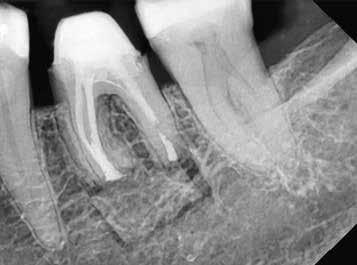

1. a-n. ábrák: Preoperatív CBCT-felvétel a bal alsó 6-os (3.6) fogról. Az axialis (a), coronalis (b) és sagittalis (c) nézeteken a mezialis és distalis gyökerek apicalis harmada körül sugáráteresztő zóna és ép buccalis corticalis csont látható. Egy olyan sablont terveztünk, amely jelezte a csontablak határait az apicalis terület pontos elérése érdekében (d). A mikrosebészeti bevatkozás során a sablont a helyére illesztettük (e), a csontablak határait megjelöltük (f) egy Piezotome CUBE LED kézi-darabba fogott fűrésszel, majd kivágtuk és eltávolítottuk (g és h) az apicalis területhez történő hozzáférés, illetve a mezialis és distalis gyökerek rezekciójának, retrográd preparációjának és retrográd gyökértömésének elvégzése érdekében (i). Végezetül a csontablakot visszaillesztettük és kollagén szivaccsal stabilizáltuk (j). A műtét után közvetlenül készített röntgenfelvétel a 3.6-os fogról (k). A kétéves kontroll során készített CBCT-felvétel: axialis (l), coronalis (m) és sagittalis (n) nézetek.

Egy 63 éves páciens korábban már kezelt bal alsó első nagyőrlőfogából (3.6) eredő mérsékelt fájdalom miatt kereste fel rendelőnket. A kórtörténetében panasza szempontjából releváns információ nem szerepelt. Az elkészült CBCT-felvételen a korábbi kezelések során észre nem vett, jelenleg feltáratlan meziobuccalis csatornát, valamint a mezialis és distalis gyökerek körül kialakult periapicalis elváltozást, és ezt a léziót borító intakt buccalis corticalis csontlemezt láttunk.

Klinikai vizsgálat során vertikális kopogtatási érzékenységet jelzett. A fog körül mérhető szondázási mélység és a fogmobilitás fiziológiás volt. A CBCT-felvételen nem észleltünk a csontos regeneráció megindulására utaló jeleket (1. a–c. ábrák). A korábban gyökérkezelt, gyökértömött és revideált 3.6-os fog esetében az alábbi diagnózis került felállításra: periodontitis periapicalis symptomatica. A panaszokat okozó fog további ellátása során navigált endodonciai mikrosebészetet kívántunk alkalmazni. Az alsó állcsontról intraorális szkent (TRIOS, 3Shape) készítettünk, és a felszíni topográfiát tartalmazó STL fájlt, valamint a CBCT-felvétel készítése során nyert DICOM fájlokat a Blue Sky Bio szoftver segítségével egyesítettük. A sebészi sablon megtervezésére az így kapott háromdimenziós képet használtuk. A sablon kialakítása során arra törekedtünk, hogy a sablon egyértelműen meghatározza a gyökércsúcsi terület eléréséhez szükséges csontablak határait (1. d. ábra)